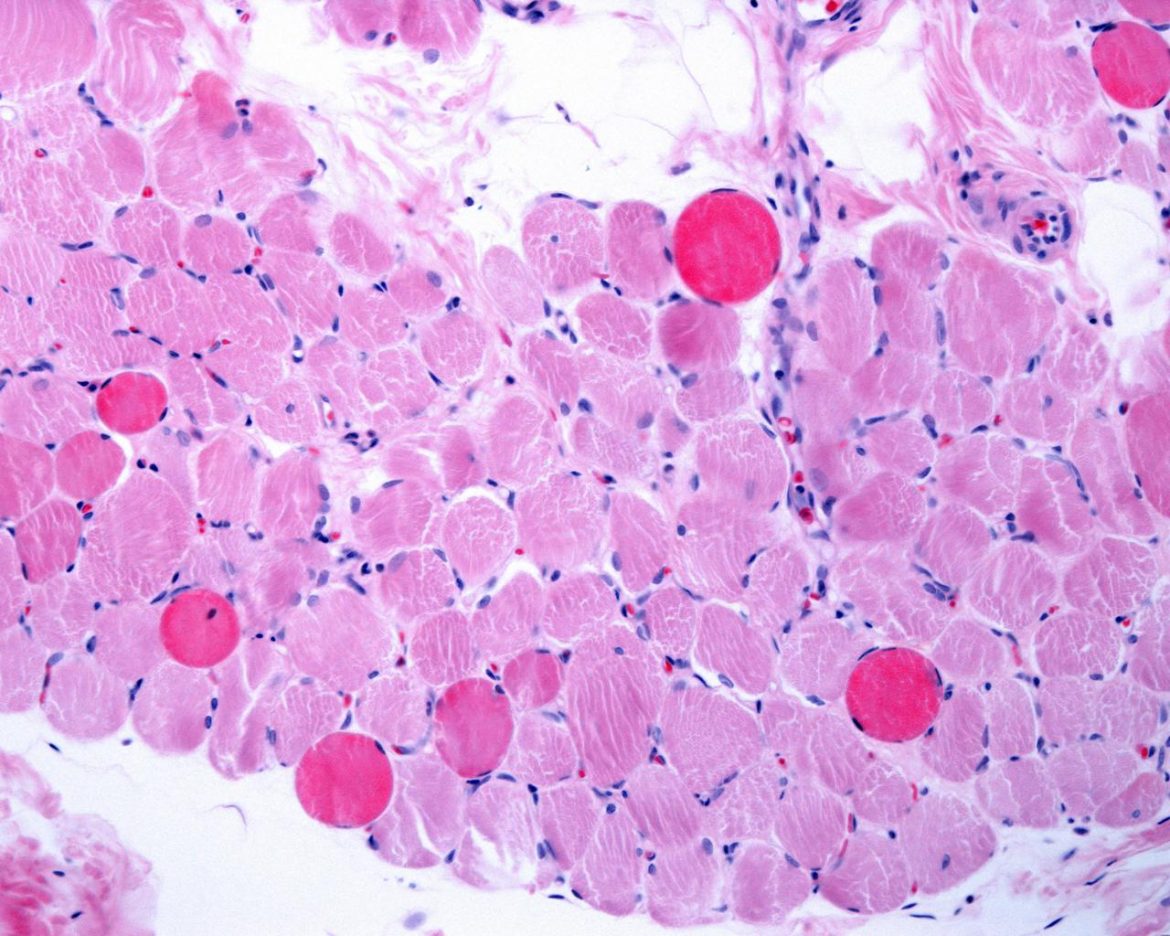

Milano, 22 lug. (Adnkronos Salute) – Dalla ricerca italiana una nuova strategia per favorire la riparazione e la rigenerazione dei muscoli nei malati di distrofia di Duchenne. La scoperta, pubblicata su ‘Nature Nanotechnology’, porta la firma di un team di scienziati milanesi. Gli autori hanno sviluppato un metodo innovativo per veicolare in modo mirato nei tessuti muscolari distrofici microvescicole (esosomi) ingegnerizzate, con proprietà antinfiammatorie.La ricerca è coordinata da Chiara Villa e Yvan Torrente del Laboratorio di cellule staminali, Centro Dino Ferrari, del Dipartimento di Fisiopatologia medico-chirurgica e Trapianti dell’università Statale di Milano e dell’Unità di Neurologia del Policlinico cittadino, in collaborazione con i gruppi di Angelo Monguzzi (Dipartimento di Scienza dei materiali dell’università di Milano-Bicocca) e di Domenico Aquino (Dipartimento di Neuroradiologia dell’Irccs Istituto neurologico Carlo Besta di Milano). “La risoluzione dell’infiammazione nel contesto delle distrofie muscolari è una delle sfide più ardue che ricercatori e clinici cercano di risolvere”, spiega Villa. Gli scienziati hanno trovato un modo per ‘indirizzare’ esosomi ingegnerizzati ad azione antinfiammatoria nei muscoli malati: utilizzando come vettore dei nanotubi ferromagnetici, questi esosomi possono migrare in maniera specifica nei muscoli danneggiati dalla distrofia muscolare di Duchenne (Dmd) tramite l’applicazione di un campo magnetico esterno dopo un’iniezione sistemica. “Siamo riusciti a controllare la biodistribuzione e il targeting degli esosomi in vivo al fine di ridurre la condizione infiammatoria dei muscoli colpiti dalla Dmd”, sottolinea Villa. Le analisi quantitative a livello muscolare hanno mostrato che i macrofagi, un tipo di globuli bianchi, dominano l’assorbimento degli esosomi iniettati, promuovendo la rigenerazione muscolare e migliorando la performance dei muscoli in un modello murino di distrofia Duchenne. “I nostri risultati – commenta Torrente – forniscono nuove intuizioni per lo sviluppo di terapie basate su microvescicole naturali e sintetiche al fine di trattare diverse forme di malattie muscolari. In generale, evidenziano la formulazione di efficaci nanovettori funzionali mirati a ottimizzare la biodistribuzione delle microvescicole”. Questa scoperta, si legge in una nota UniMi, rappresenta “un significativo passo avanti nel campo della medicina rigenerativa e delle terapie innovative per malattie muscolari. Il controllo preciso della biodistribuzione degli esosomi apre” infatti “nuove possibilità per il trattamento non solo della distrofia muscolare di Duchenne, ma anche di altre patologie muscolari caratterizzate da infiammazione cronica e degenerazione tessutale. La combinazione di nanotubi ferromagnetici ed esosomi ingegnerizzati potrebbe rivoluzionare l’approccio terapeutico, offrendo speranze concrete per pazienti e famiglie affetti da queste malattie debilitanti”.